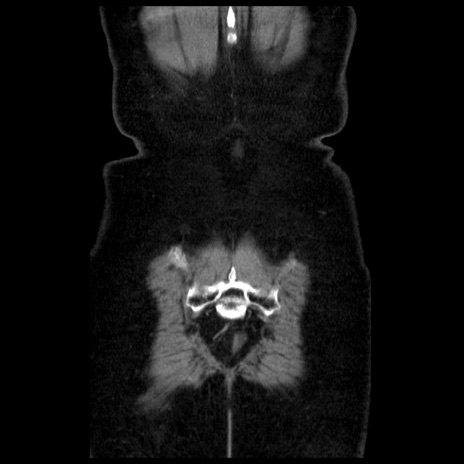

症例13(冠状断像)

【症例】70歳代女性

【主訴】腹痛、嘔吐

【現病歴】15時間程前(昨晩)より腹痛あり。今朝になっても症状の改善なく、嘔吐あり。腹痛も増悪あり、救急外来受診。

【既往歴】子宮癌全摘術後

【身体所見】意識清明、BP 121/72mmHg、P 74bpm、SpO2 100%(RA)、腹部:平坦・軟、腸雑音ほぼ聴取せず。下腹部・心窩部・臍左上に圧痛あり。反跳痛なし。

【データ】WBC 10600、CRP 0.15

横断像